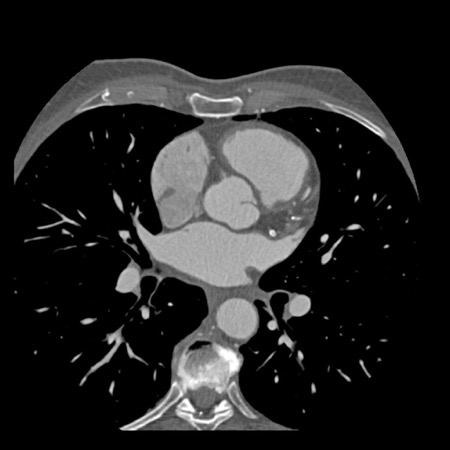

Modifier S – stent

The presence of a stent is indicated by modifier “S”.

Examples

- If a patient has a stent, showing no in-stent restenosis and a mild

(25-49%) stenosis in the coronaries, this patient classifies as CAD-RADS

2/S. - Similarly, a patient with no in-stent restenosis but severe (70-99%)

stenosis in a coronary other than LM classifies as CAD-RADS 4A/S. - If there is a severe (70-99%) in-stent restenosis in a coronary other

than LM, this patient classifies as CAD-RADS 4A/S. - If the stent is non-diagnostic and there is no >49% stenosis present

in the coronaries, the patient classifies as CAD-RADS N/S.

Note: the location of the stenosis does not matter, when using

CAD-RADS.

What matters is that the patient has a severe stenosis and needs further

management.

Please note: total coronary plaque burden should also be added and is

placed before the modifier S.